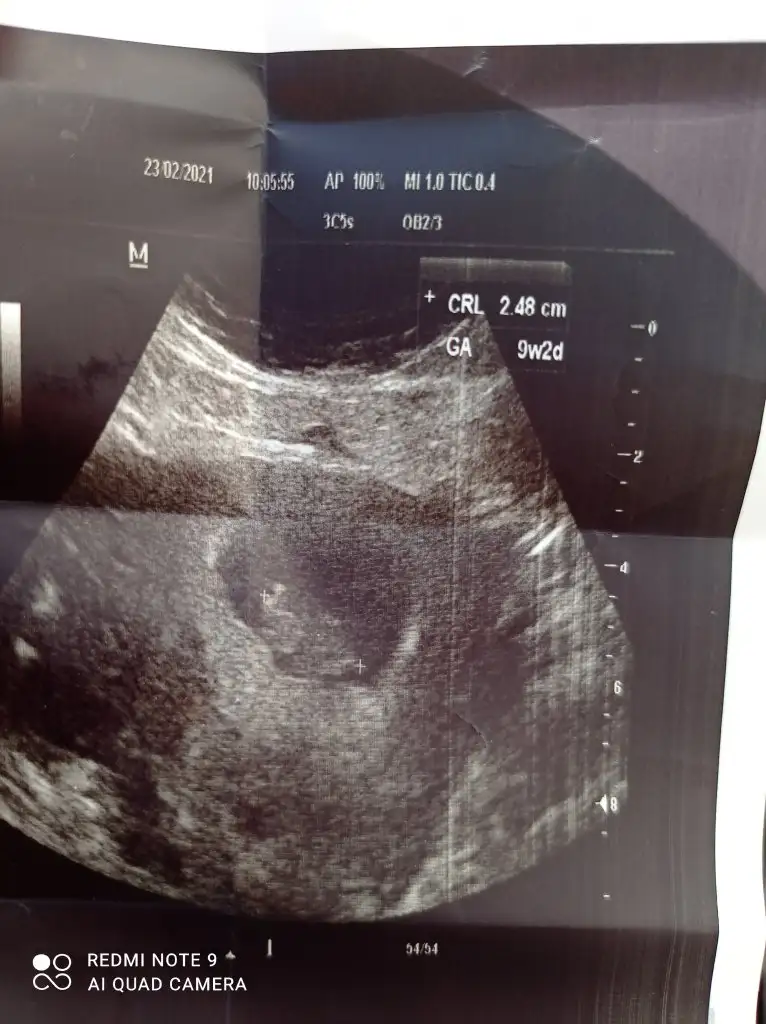

Selam cnm bana kız demiştin ama dr haftaya bakarız dedi belli olunca burdan yazıcam sana. Arkadaşımın ultrason reminede bakarmısın. karından bakılmış.

• IMG_20210227_130432.webp

21,6 KB · Görüntüleme: 71

• IMG_20210227_130403.webp

16,4 KB · Görüntüleme: 85